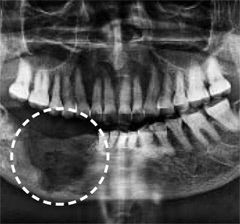

골다공증 치료제 투여 부작용으로 턱뼈가 괴사한 모습.  경향신문 자료사진